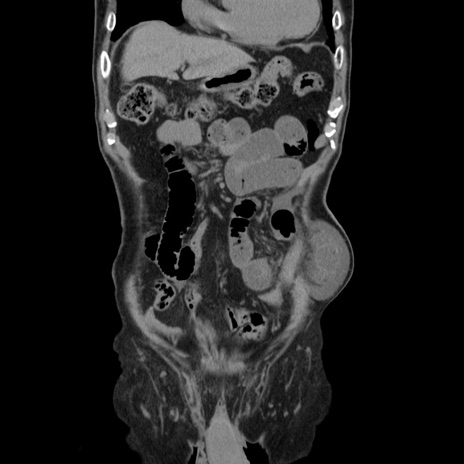

症例24(冠状断像)

【症例】80歳代男性

【主訴】左側腹部痛、嘔吐

【現病歴】本日早朝より左腹部に痛みあり。昼頃嘔吐認めたため、救急要請。

【既往歴】直腸癌(Mile手術)、胆摘

【身体所見】意識清明、BT 35.9℃、BP 221/93mmHg、SpO2 97%(RA) 、腹部:左ストーマ周囲に限局性の腹部膨隆あり。 膨隆部自発痛・圧痛あり・軟。

【データ】WBC 7700、CRP 0.09